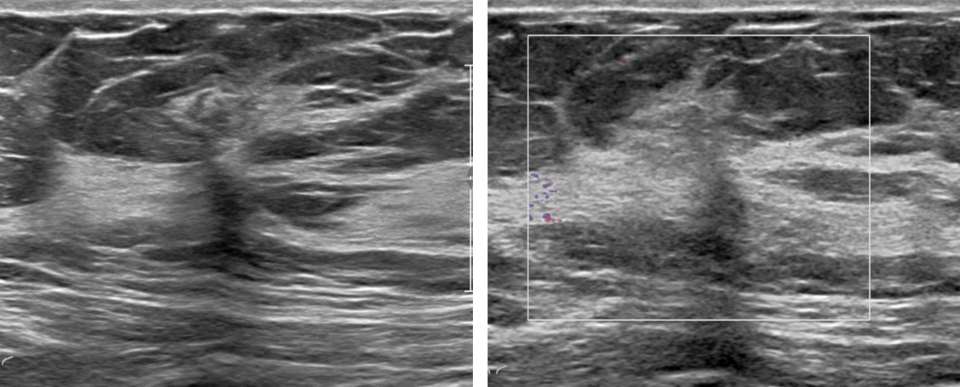

Ultrasound:

Radial sclerosing lesions have a variable appearance on ultrasound imaging and are frequently not visualized. They are typically found on targeted ultrasound examination for a mammographically detected lesion. When they are seen, they may present as an irregular hypoechoic mass or parenchymal distortion with ill-defined borders +/-posterior acoustic shadowing (Fig 1b). They may also present as a round or oval mass (Fig 2b) or a focal area of shadowing without a discrete mass. Findings that do not confirm but may favor a RSL over carcinoma include the absence of an echogenic halo, shadowing, or breast architectural distortion and/or the presence of tiny cystic changes(2,3).